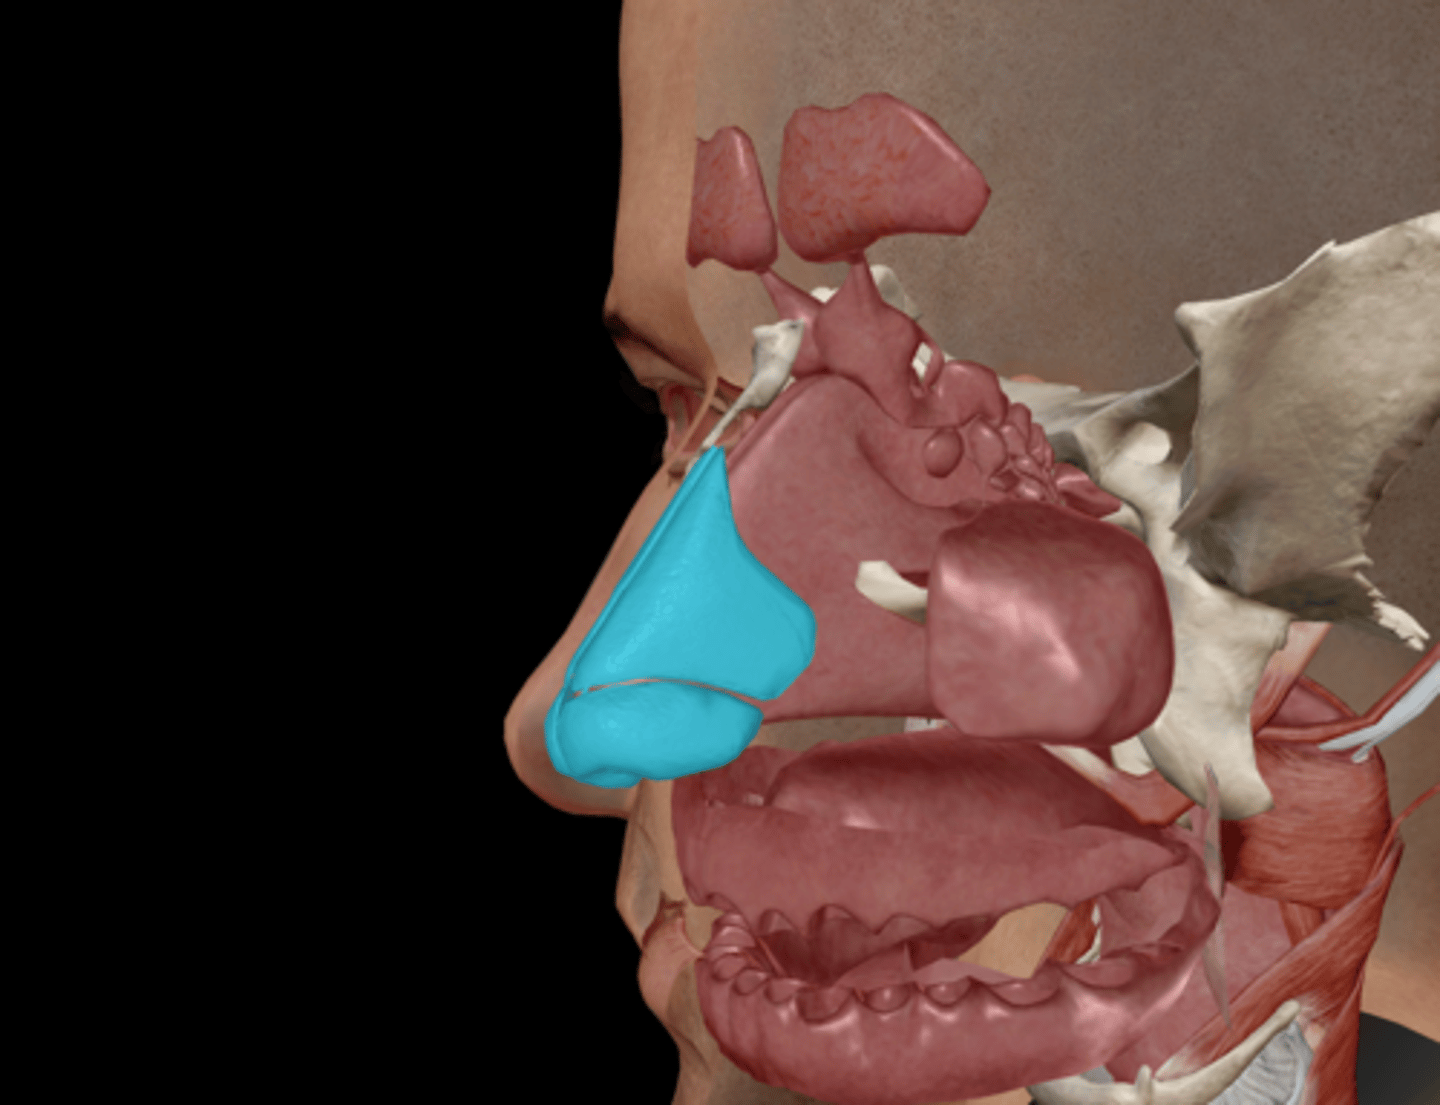

Nasal cartilages